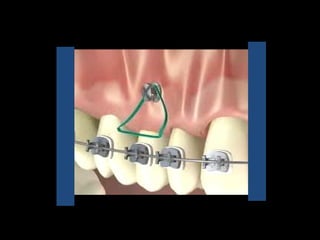

Mini-implantes Odontit

Mario Herzberg

Buenos Aires

Mini-implantes para apoyo de fuerzas ortodóncicas

Mini-implantes para apoyode fuerzas ortodóncicas